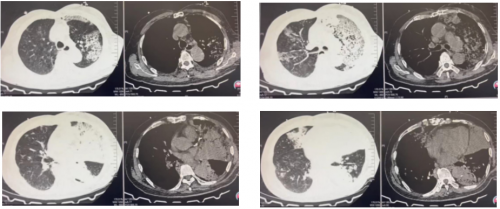

胸部CT检查:

双肺多发斑片影,左肺为著,纵隔内未见肿大淋巴结影,主动脉及冠状动脉硬化,胸部术后改变。